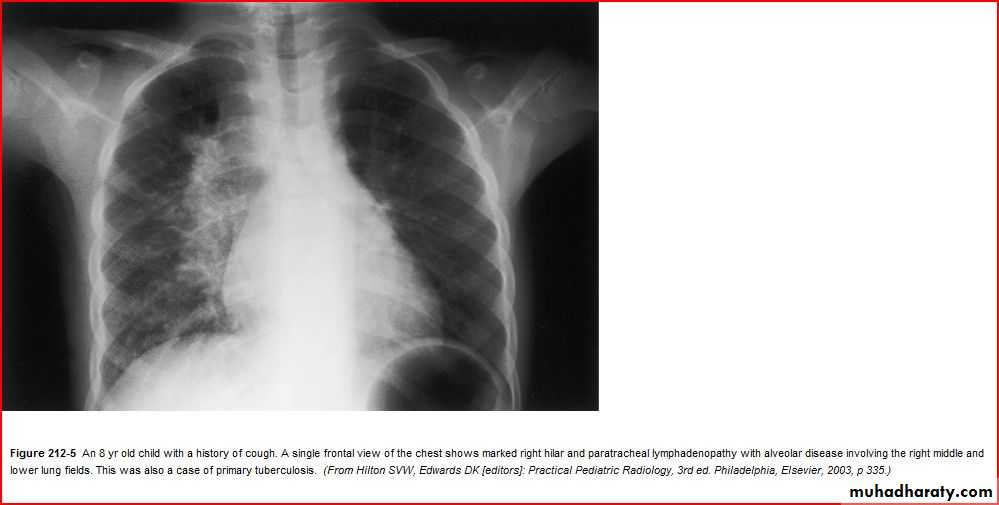

Enlarged hilar lymph nodes + non hemogenous opacity of middle and lower lobe

TBPleural effusion meniscal sign